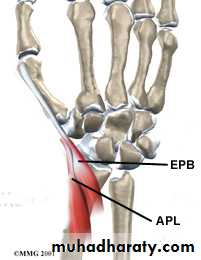

De Quervain`s disease

Tenosynovitis of the compartment of APL & EPBCause : overuse

CF : middle aged femalepain & swelling over radial styloid

Finkelstein t.

Rx : NSAIDS

steroid injectionsurgery